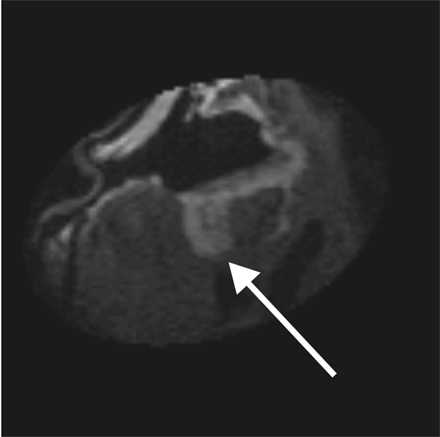

Both patients underwent IMRI-guided resection of their tumors. Preoperative MR imaging demonstrated the targeted lesion. Intraoperative MR without gadolinium, following the prior administration of ferumoxtran-10, easily provided images that demonstrated the lesions seen on preoperative MR images obtained in both patient 1 (Fig 1) and patient 2 (Fig 2). In one operation, post-resection imaging revealed a persistently enhancing area that was then resected (Fig 3). Even in the low-field-strength IMRI system, ferumoxtran-10 provided adequate imaging of the lesions in both of these patients. Postoperative MR images obtained in both patients had no significant enhancement with gadolinium, which suggests resection of the enhancing tumor bulk (Figs 4 and 5). Both postoperative MRIs show high T1 signal intensity in the wall of the resection cavity. The walls of the cavities, however, do not appear to enhance significantly with gadolinium. Figure 5 also shows the resection cavity itself filled with T1 hyperintense material. The cause of this residual T1 hyperintensity, either from blood or ferumoxtran, is unclear. Iron staining of one patient’s lesion demonstrated iron accumulation within peritumoral reactive cells (Fig 6).

Intraoperative post-resection T1-weighted MR image from patient 2, demonstrating residual enhancing lesion posteriorly (arrow). This lesion was then localized by using integrated frameless stereotaxy and resected.